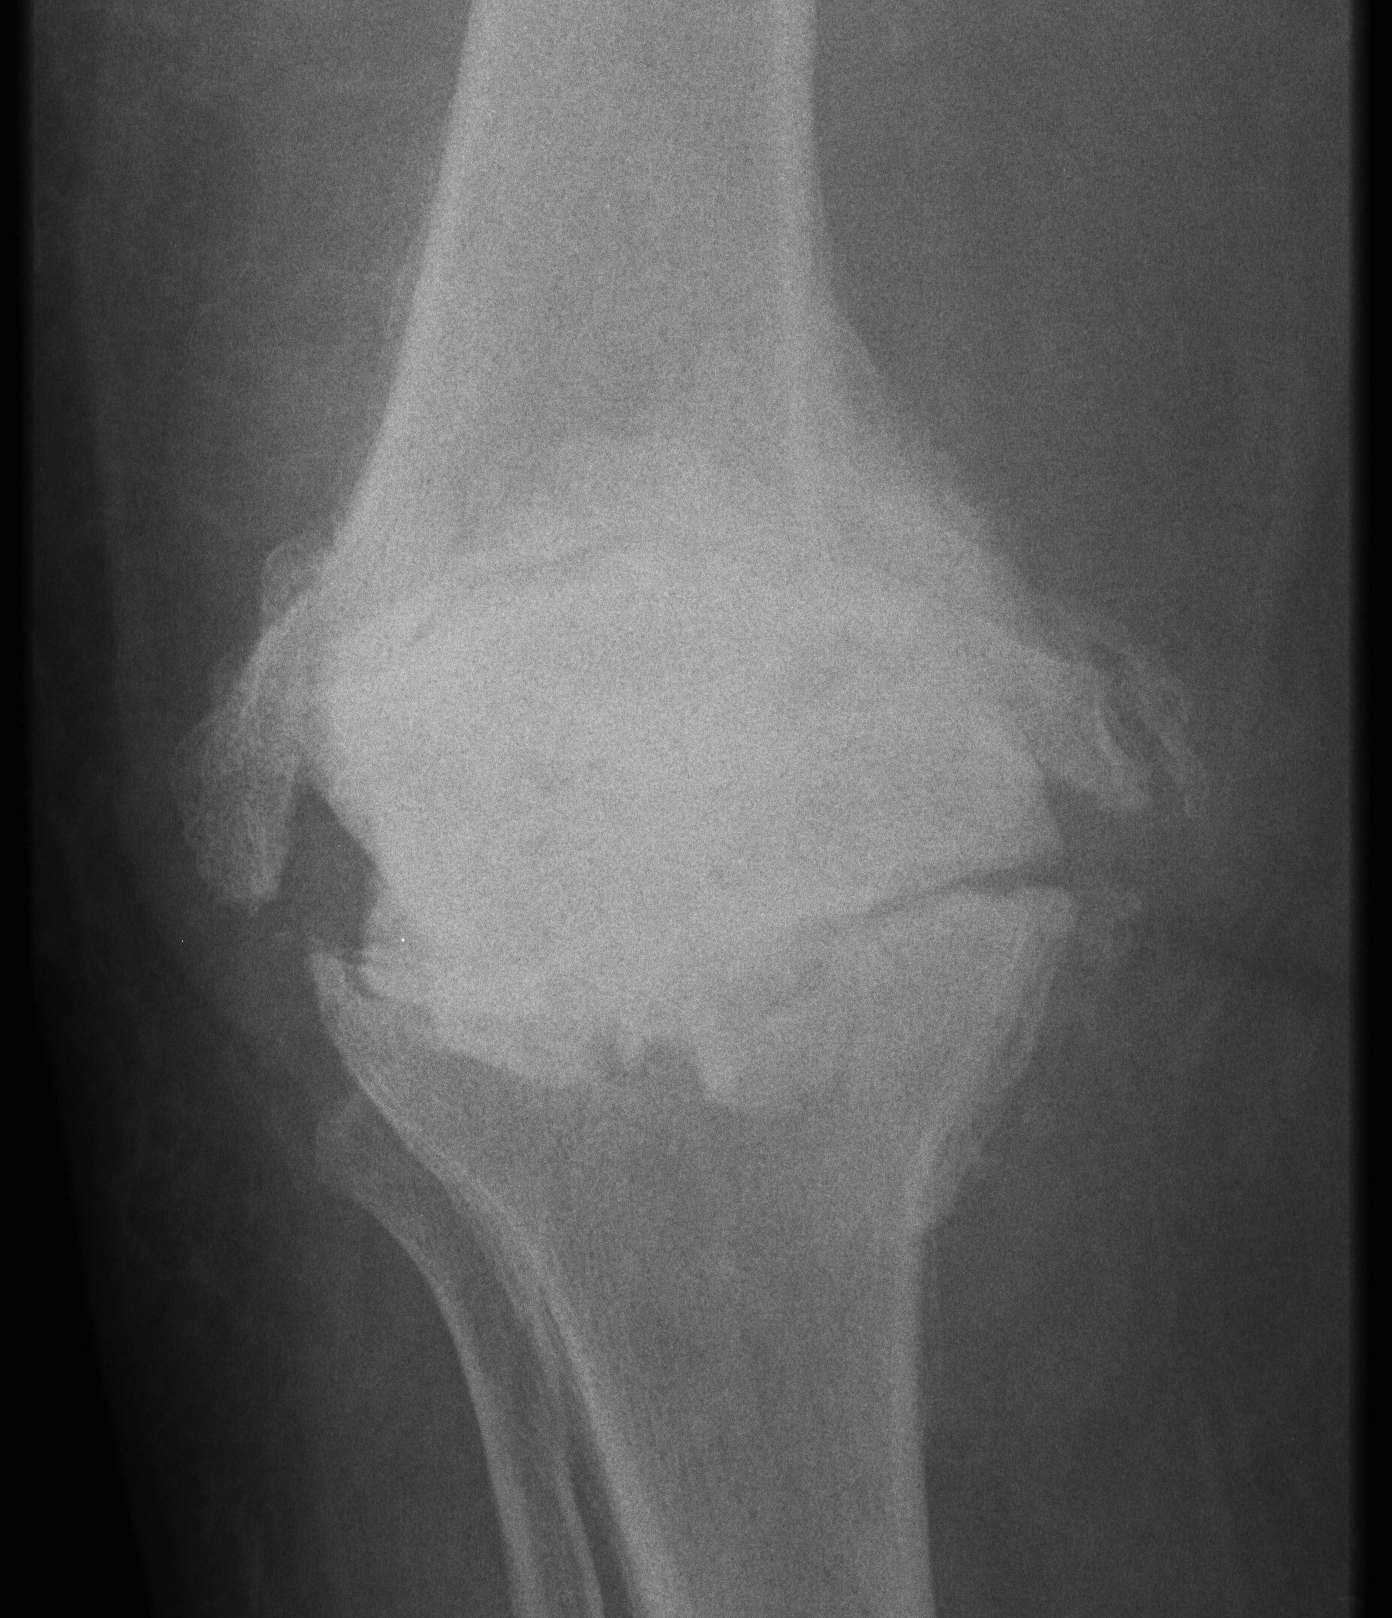

Xray

- progressive early lysis

Classification

Gustilo 1993

2. Late Post-operative

- indolent (low virulent)

- > 1/12

- well patient with healed wound

- worsening of pain / stiffness

- never pain-free interval